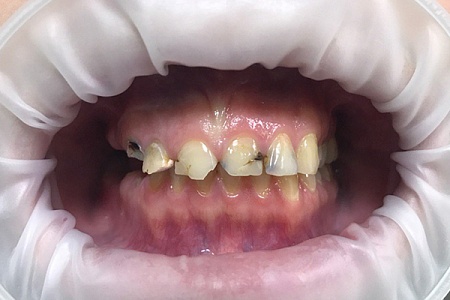

Работы наших врачей